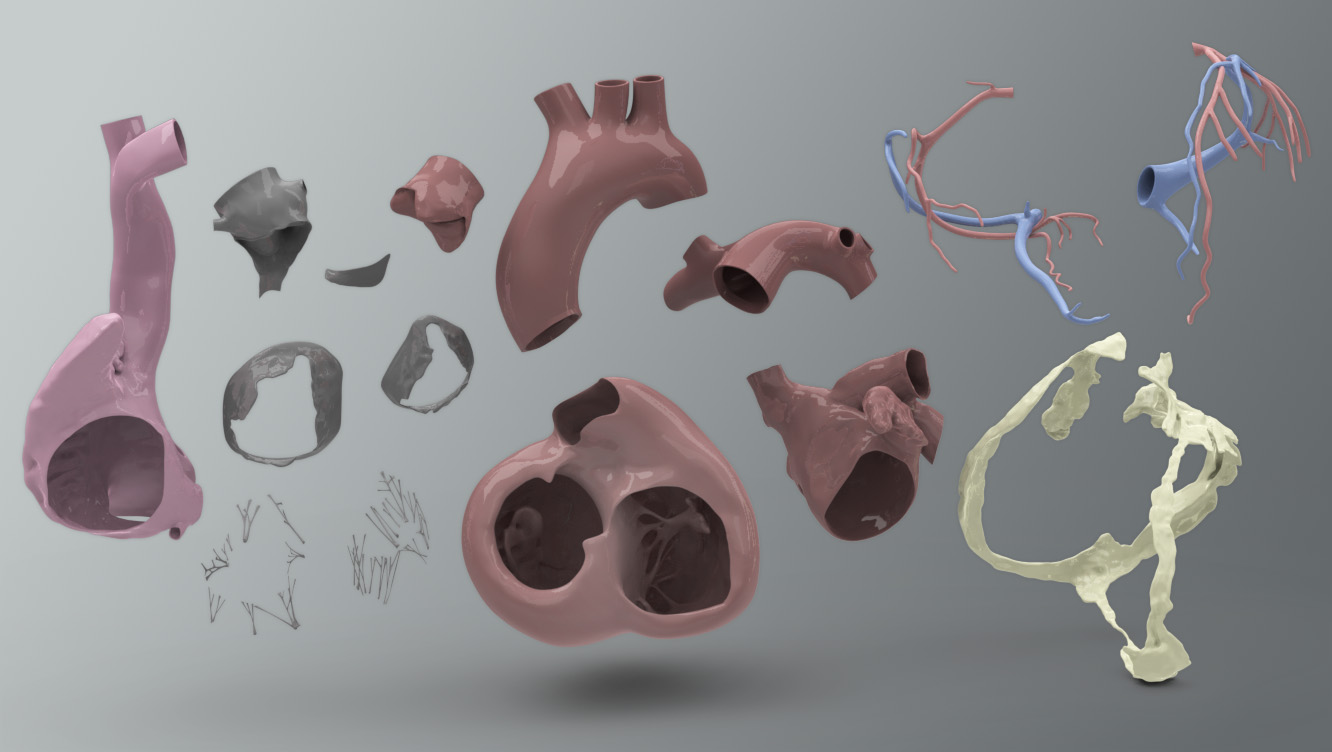

3D dissected human heart model - TurboSquid 1361664  10 Realistic Heart Drawings and Tattoos â Simple Human Heart Sketch for 2022 | Do It Before Me

Human Heart Cutaway Anatomy 3D model section | CGTrader  Human Heart by Mutantenmaid on DeviantArt

3d model heart anatomy  3d human heart anatomy model

3d human heart anatomy model  3d human heart section

3d human heart section  human heart solidworks 3d model